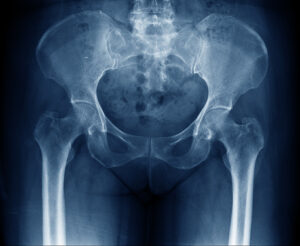

Düşme veya travma sonucu uyluk kemiğinin üst kısmında meydana gelen ciddi bir yaralanmadır. Kalça kırığı yaşlı bireylerde osteoporoz nedeniyle daha sık görülür. Belirtileri arasında şiddetli kalça ağrısı, hareket kısıtlılığı ve bacağın dışa dönmesi yer alır. Tedavi, cerrahi müdahale ve sonrasında fizik tedavi ve rehabilitasyon süreçlerini içerir. Kalça kırıkları, hızlı tıbbi müdahale gerektiren ciddi yaralanmalardır.

Yaşlılarda, kemiklerin zayıflaması (osteoporoz) nedeniyle düşmeler yol açabilir. Bu tür kırıklar genellikle evde, banyoda veya merdivenlerden düşme sonucu meydana gelir. Trafik kazası, spor yaralanması ve darbe gibi travmatik olaylar gençlerde neden olabilir. Kemik yoğunluğunun azalması, kemiklerin kırılgan hale gelmesine neden olur. Bu durum, özellikle menopoz sonrası kadınlarda yaygındır ve hafif darbeler bile kırıklara yol açabilir. Ailede osteoporoz veya kırık öyküsü olan bireylerde kalça kırığı riski daha yüksektir.

Kalçada ve çevresindeki kemiklerde bulunan kötü huylu tümörler, kemiklerin zayıflamasına neden olabilir. Kasların zayıf olması, düşme riskini artırır ve bu da kırıklara yol açabilir. Yetersiz kalsiyum alımı, sigara ve alkol kullanımı, hareketsiz yaşam tarzı kemik sağlığını olumsuz etkileyerek riski artırır. Parkinson hastalığı, felç gibi nörolojik rahatsızlıklar denge ve koordinasyonu etkiler düşme riskini artırır. Kalça kırığı ciddi yaralanmadır ve tedavi gerektirir. Erken tanı ve uygun tedavi, iyileşme sürecini hızlandırabilir. Komplikasyonları azaltabilir.